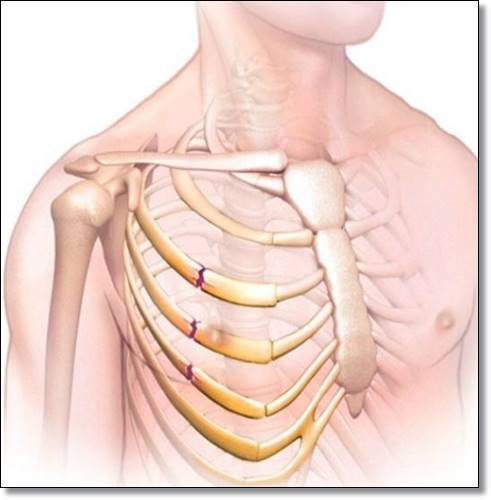

갈비뼈 금이 가거나 부러졌을 때 증상은?

뼈가 부러진게 아닌

살짝 금이 간 정도라면 통증이 심하지 않을 수 있습니다.

살짝 금이 간 정도를 벗어나서 부러진 경우에는 정말로 조심하셔야 한답니다.

부러진 갈비뼈의 뾰족한 부분이 신체 내의 다른 장기들을 찌를 수 있기 때문이랍니다.

폐를 찌르게 되면서 공기나 피가 새어 나올 수가 있답니다.

그렇게 되면 호흡곤란, 저혈압, 수술 등을 해야 하는

상황으로 번질 수도 있기 때문에 조심하셔야 한답니다.